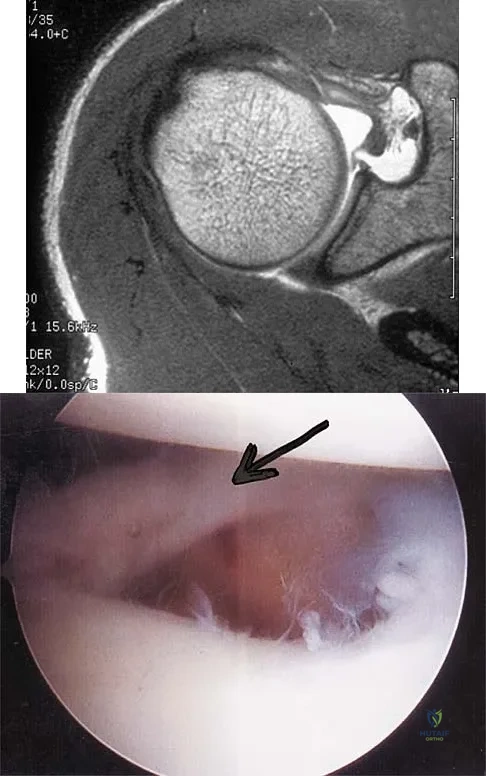

A patient has right shoulder pain. Figure 1a shows a gadolinium-enhanced transverse MRI scan at the level of the coracoid. Figure 1b shows an arthroscopic view of the anterior structures from a posterior portal. These images reveal which of the following findings?

Explanation